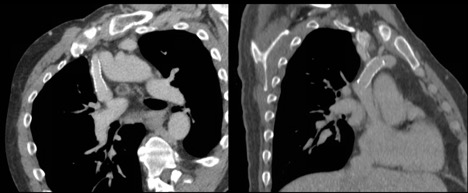

[3]Figure 1. Oblique reformatted chest CT demonstrating nonocclusive stenosis of the distal portion of the SVC. Note the synechiae or "web" within the innominate vein.

[4]Figure 2. Axial chest CT demonstrating occlusive stenosis of the central portion of the innominate vein and SVC confluence.

Given his chronic immunosuppression, he was admitted by internal medicine for initiation of intravenous (IV) antibiotics. Thoracic surgery, transplant infectious disease, and nephrology were consulted following admission. He underwent an echocardiogram, which did not demonstrate congestive heart failure. A computed tomography (CT) scan demonstrated right internal jugular occlusion, superior vena cava (SVC) stenosis, prominent thoracic venous collaterals, and cervical and mediastinal lymphadenopathy (Figures 1 and 2). His pleural fluid cytology and cultures were negative, but testing indicated the presence of chylomicrons and his triglyceride level was 1154 mg/dL, which was consistent with a chylothorax.